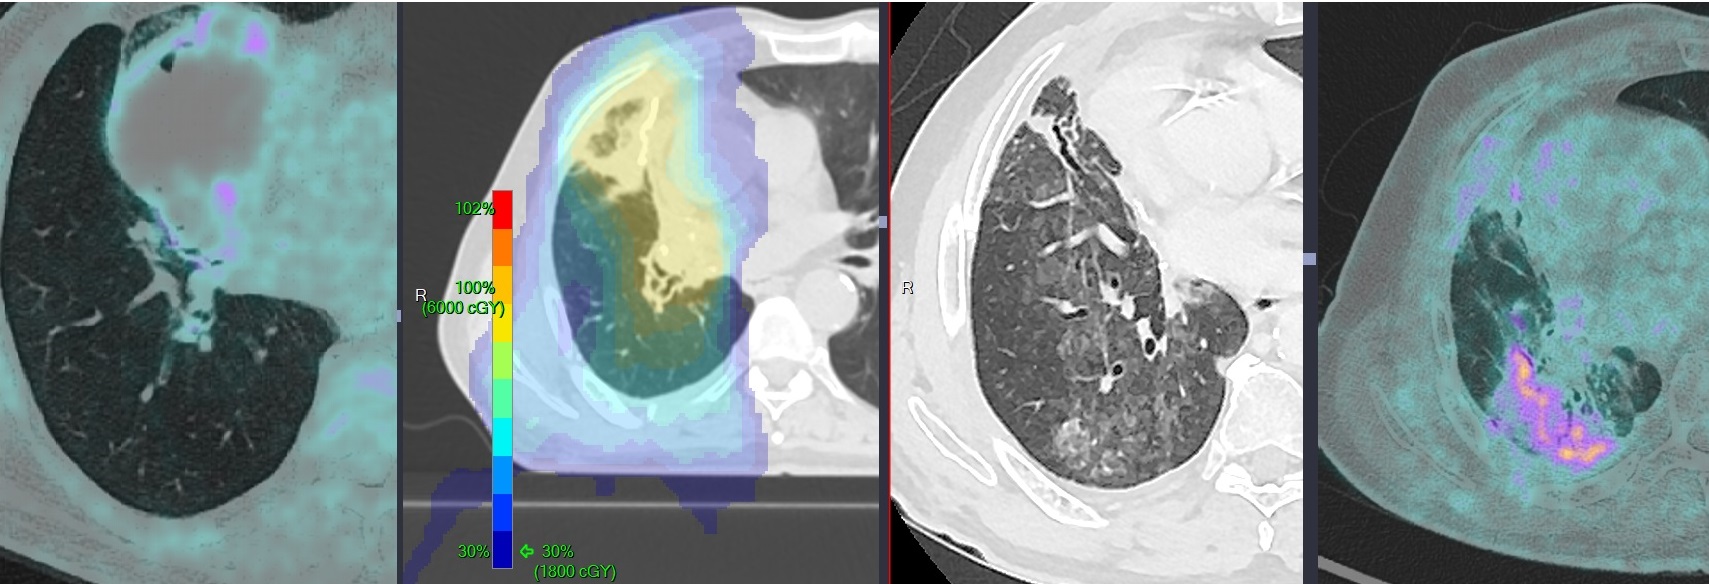

Pneumonie Post-Radique Aigue

- Surivent dans les 4 à 12 semaines de l’irradiation

- Chercher le champ d’irradiation

- Forme de pneumonie orgasinsée sur domage alvéolaire → finit en fibrose

- Condensations nodulaires, verre dépoli

Séquelles Chroniques de Radiothérapie

- Séquelle à long terme (condensations, bronchiectasies)

- Chercher la récidive en bordure

Cas

postradique sequelle stigmate radiotherapie post-radique stigmates

OP organizing pneumonia pneumonite radique postradique radiation radiation therapy